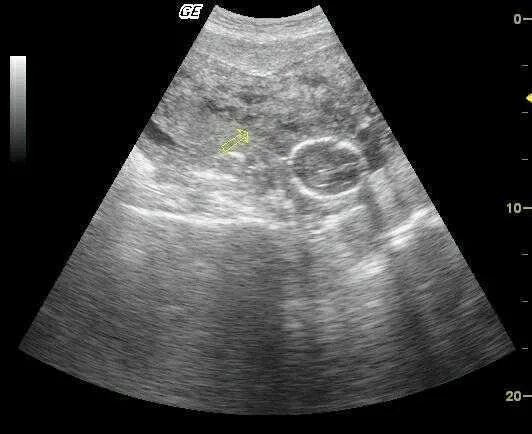

Утолщение стенки миометрия